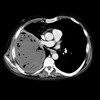

17

Q